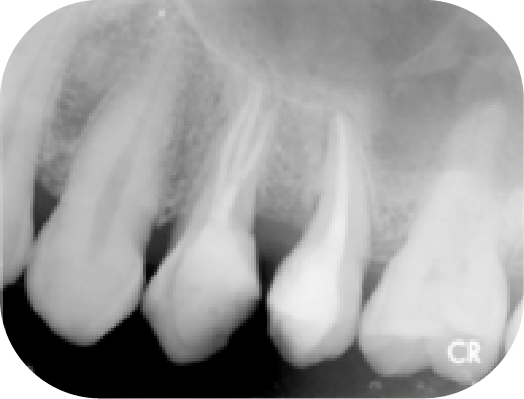

病人因其他院所醫師無法定位根管位置被轉診,在顯微鏡底下可以發現短短不到兩毫米的距離藏有兩根根管(圖中紅線標示處),這是傳統根管治療很難發現的。